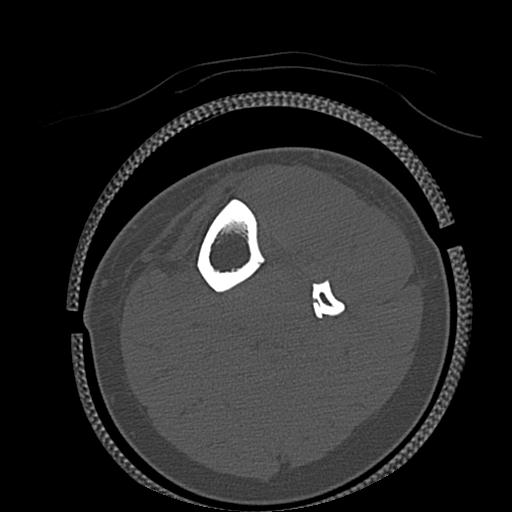

110211 1/6 1/8 左前腕 4R 15歳男性 橈骨骨幹部骨折